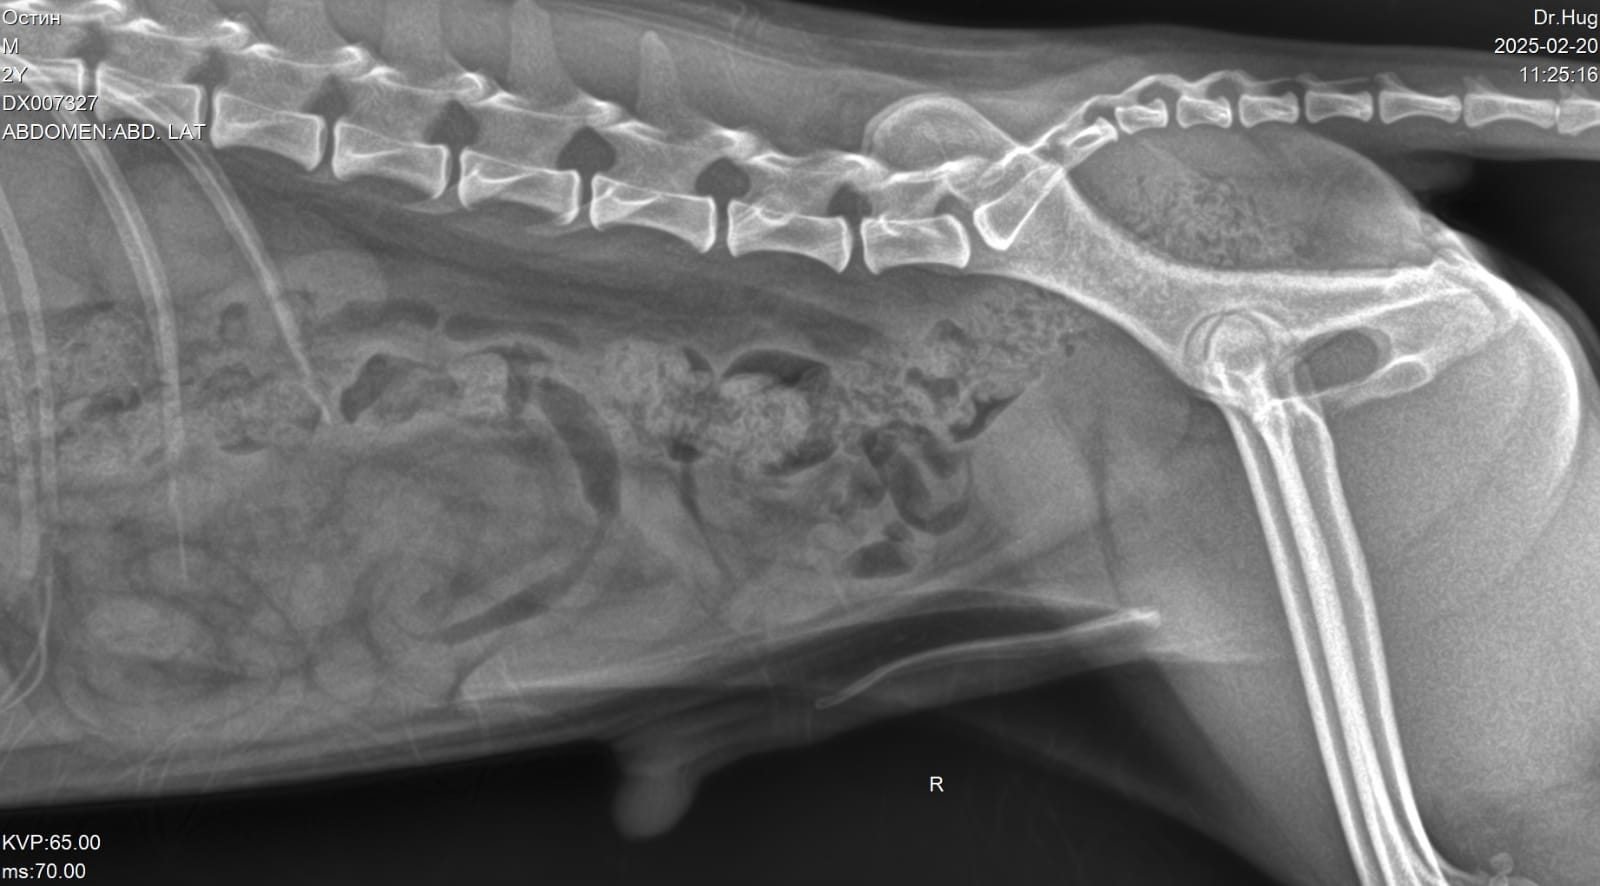

Светлана с Остином посетили врача.

Вложения

Еще